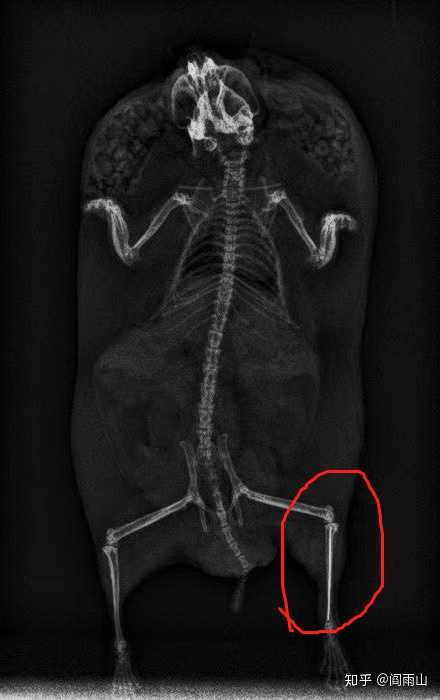

仓鼠后腿骨折内固定,会相对硬核一些(广州立德动物医院)

图片尺寸440x700